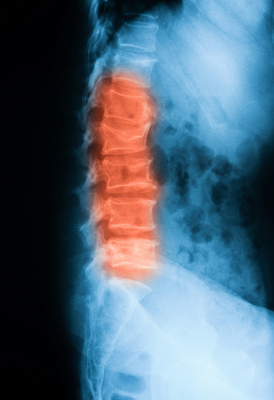

Чтобы определить, как конкретно позвонок сломан, насколько обширно повреждение, травматолог использует методы аппаратной диагностики:

- рентгенография;

- компьютерная томография;

- магнитно-резонансная томография.

КТ и МРТ — более точные методы, поскольку позволяют получить детальное изображение позвоночника.

- рентгенография — позволяет определить поврежденный позвонок;

- компьютерная томография — предназначена для детального осмотра структуры позвонка;

- МРТ — детально показывает наличие повреждений нервных тканей позвоночного столба;